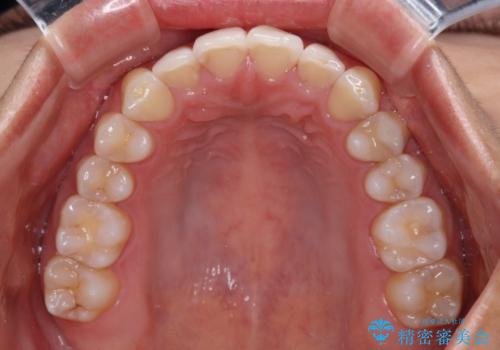

前歯の重なりをインビザライン・モデレートで矯正治療

- インビザライン・モデレート

- 1年2ヶ月

インビザライン・モデレートは、製作できるアライナーの枚数に制限があるため、移動可能な量に限りがあるものの、インビザライン・ライトよりも枚数が多いため、幅広い症例に対応可能です。